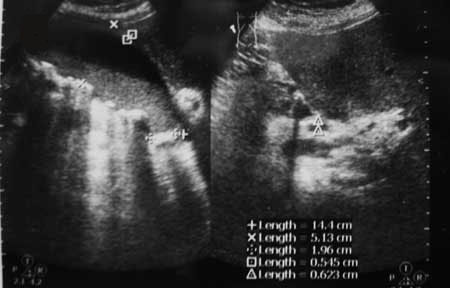

Женщина А. поступила в приемный покой с жалобами на сильные боли в правом подреберье

- IMG_6752w.jpg (48.26 КБ) 3108 просмотров

Ваше заключение?

Инга,камни в пузыре я увидела-т.е.калькулёзный холецистит имеется.А вот 2-й снимок нечёткий,я подозреваю там снимок холедоха.Правильно?

Да, холедох

В первом случае-

острый калькулезный холецистит (размеры ЖП увеличены, стенка утолщена); во втором -

хронический. Или еще что-нибудь?

Тольк0 в первом случае можно предположить не просто острый холецистит, а острый гангренозный холецистит, эмпиему ЖП.